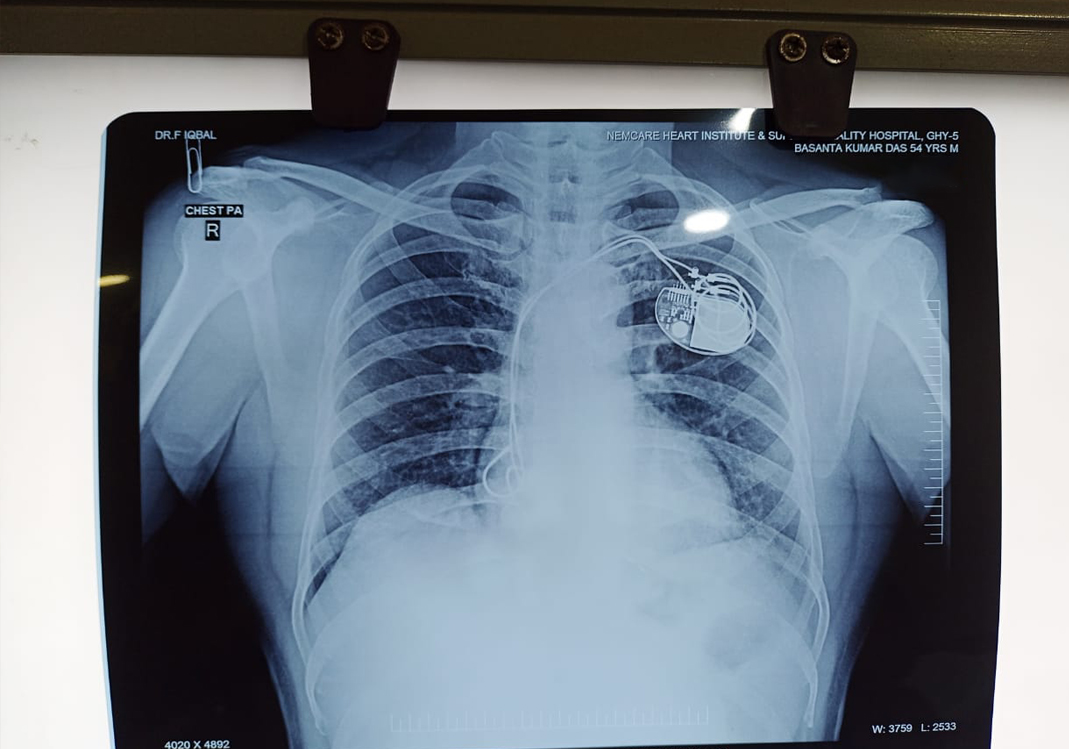

My father, a loving and hardworking man, has always been the pillar of our family — full of life, laughter, and strength. But recently, he suffered not just one, but two heart attacks, leaving his heart critically weak. Doctors had to urgently implant a pacemaker to save his life.

We thought he was on the path to recovery… But soon after, things took a painful turn. The pacemaker’s lead failed. A second emergency operation was performed, but sadly, it didn’t succeed.

Now, he needs a third, life-saving heart operation — and it must happen soon.